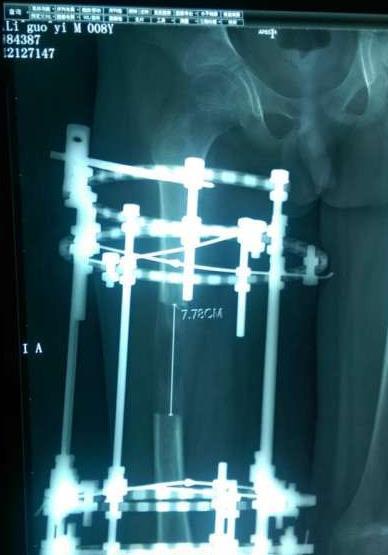

断骨增高术是上世纪末在国内风靡一时的一项手术,给许多个子不高的人带来了希望,却也让许多人留下了终身的遗憾,这项手术风险大,术后并发症的几率非常高,造成肢体畸形。近年来随着国家卫生部门对该项手术的严格限制与管理,合法开展该手术的医疗机构已经很少,且受术者多为存在先天下肢畸形的患者,可惜的是,还是有一部分单纯是以美容目的。

断骨增高术的原理很简单,就是将正常的骨骼弄成骨折,将骨折的骨骼两端中间间隔微小的距离,利用骨组织强大的愈合能力,填补间隔的微小缝隙,达到增高的目的。虽然手术的原理很简单,但是成功率并不高,而且有可能造成腿部坏死、下肢瘫痪等严重后果,所以只是单纯为了美型长高而选择这种方法的患者要慎重考虑。